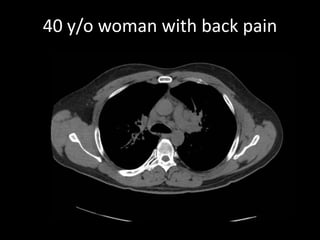

A 52-year-old man underwent a CT FDG PET fused PET/CT scan for a palpable lump. A 40-year-old woman with back pain received MRI scans including STIR, T1, and contrast images. Another patient, a 75-year-old woman with osteoporosis, also received imaging.